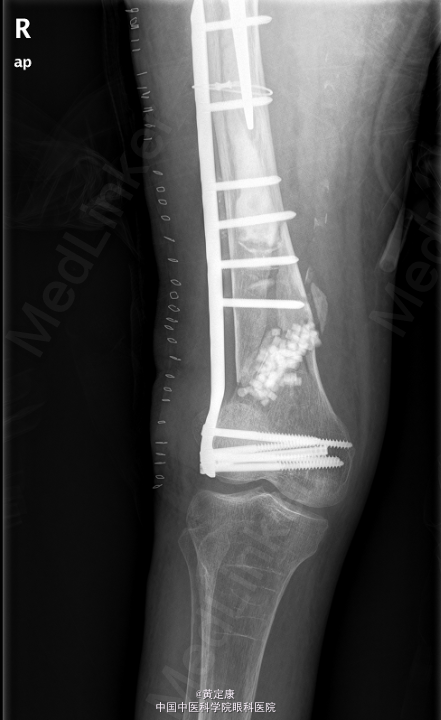

患者,女,82岁,因“摔伤致右下肢疼痛伴功能受限1天”入院。 患者1天前因外伤致右下肢剧烈疼痛,无法行走,。送至外院急诊,X线示“右股骨髁上骨折”,拟“右股骨髁上骨折”收治入院。

右膝部肿胀,膝关节活动受限,右足各趾活动感觉正常,末梢血运正常。石膏固定。检查提示:右股骨髁上骨折。

初步诊断: 右股骨髁上骨折 行[右]股骨骨折切开复位钢板内固定术